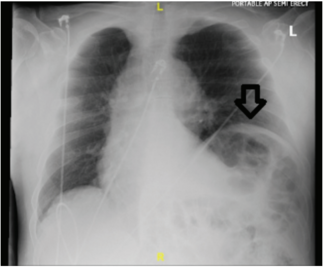

Saiyeda S. Ali, MD; Greeshma Molugu, MD; Ruben Abreu, MD; Asad Rizvi, MD; Mehdi Khalafi, MD

A 56-year-old male with a past medical history of gastroesophageal reflux disease and tobacco abuse presented to the emergency department with a chief complaint of chest pain and progressive shortness of breath of a year duration. The patient...